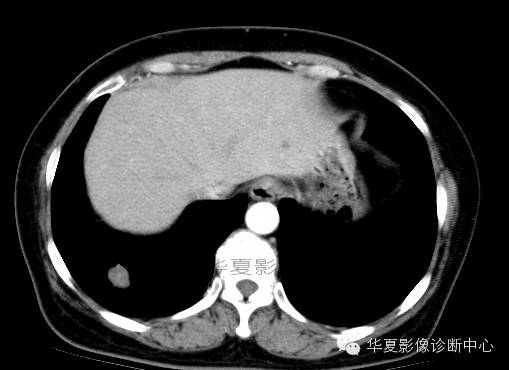

影像资料:

术中切除(右下)部分肺组织7x6x2cm,切面见一灰白色肿物,直径2cm,质较脆,与周围组织界限清,略呈分叶状,无包膜。

(右下肺)错构瘤(以软骨成份为主)

肺错构瘤多发生在胸膜下肺表浅部位,呈球形、椭圆形,有完整的包膜,质硬,易与周围肺组织分开。肺错构瘤的直径0.5~12cm,多数小于3cm。肿瘤剖面呈灰白色,质硬,有黏液和囊腔。主要成分有软骨、腺体、平滑肌、脂肪及纤维组织等。肿瘤可发生钙化,多位于中心,分布较均匀,此种钙化结构常像爆米花样或核桃肉样。